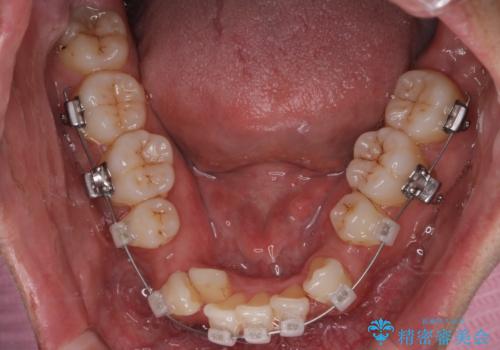

- クリア装置

- 治療計画

叢生量が大きいため、上下顎両側4番を抜歯しました。矯正治療による歯肉退縮の著しい悪化もなく、主訴であるガタつきも改善できました。